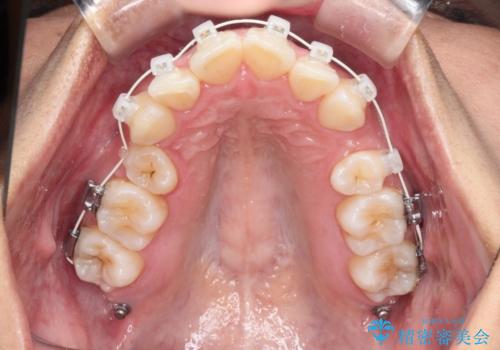

- 矯正装置

- 審美装置

- 前歯の凸凹を主訴に来院されました。

抜歯を行い、ワイヤー矯正にて治療を行いました。

凸凹もなくなり、歯磨きもしやすくなったと喜んでいただきました。

CTにて骨を確認し、側切歯の歯根をこれ以上頬側に出せないことを確認しています。